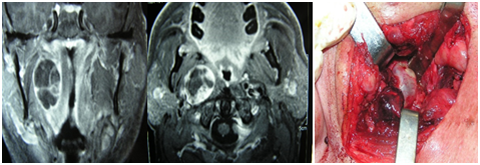

Six patients had neurilemomas located at the neck. The symptom was cervical tumor in all cases, and also disphagia in two of them. In three cases, the tumor was located at the retro-styloid carotid space. They were evaluated with tomography and magnetic resonance with contrast, and in two of them a fine needle aspiration was done with ultrasound guidance; the result was non-specific. There were not alterations in mobility of vocal cords.

In two bulky neoplasms, a displacement of the amygdala and soft palate towards the midline was observed. A transcervical approach was performed in all patients, and in two of them the exposure was extended by dissecting the posterior sector of the submaxillary gland, which was preserved.

Two tumors were originated from the cervical sympathetic chain and in another case the nerve of origin could not be specified. The resections were total and two patients had a postoperative Claude-Bernard-Horner syndrome, and one also had a “first bite” syndrome (pain in the parotid gland or in the temporomandibular joint when chewing the first time in each ingestion that decreases in successive bites) (Figure 4–6).

Figure 4 Neurilemoma originated at the cervical sympathetic chain, in the retro-styloid carotid space. Transcervical approach: complete resection.

Figure 5 Schwannoma originated at the cervical sympathetic chain in the retro-styloid carotid space. Transcervical approach: complete resection.

Figure 6 Neurilemoma originated at the carotid space.